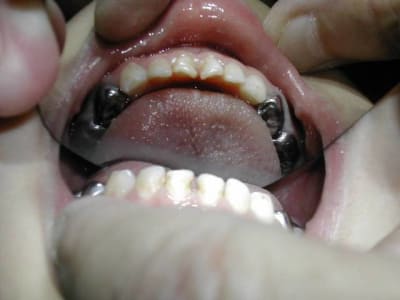

Pour garder l'éspace après éxtraction des C. on fait un arc passif en ligual soudé sur des bagues de 6.

C'est un peu plus difficil en exercice omnipratique, mais il y a des labo Ortho qui font celà très bien.

Il suffit de mettre des élastiques séparateurs entre 6 et 5 de lait, de choisir la bague nue (une boite complète n'est pas chère) de prendre l'empreinte avec les bagues et de l'envoyer au labo.

A vérifier tous les 6 mois, ou tous les ans, et de changer l'arc s'il prend du jeu au niveau du cingulum de incisives.

P.S.: L'arc soudé aux 6 est lingual. Le stop est le contact avec le cingulum des incisives. Tout est faible à cet age, aussi bien l'ancrage osseux que les forces musculaires.

En cas d'éxtraction de 54/64, je ferais Bagues sur 6 + arc lingual. Mais on peut aussi faire deux mainteneurs d'éspace, dans certains cas.

GC FUJI 1 pour le scellement

pour le suivi,regarde sur la pano le stade d'evolution des premolaires;en general,une visite tous les 3 mois cela suffit